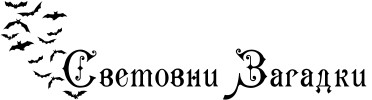

Сперматозоид се придвижва по фалопиевата тръба към яйцеклетката.